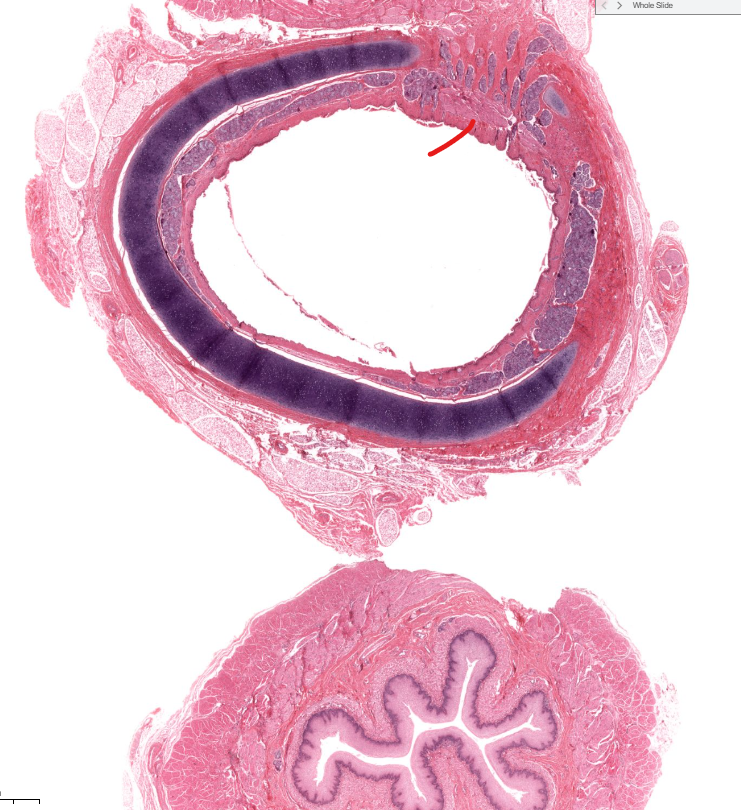

epiglottis

tissue type

strat. squamous non-keratinized epi

found on anterior/lingual surface of epiglottis

(tissue type)

respiratory epi

aka ciliated pseudostratified epithelium

found on posterior/trachea side of the epiglottis

trachea

air to lungs

has respiratory epi on the lumen

C shaped cartilage with muscle to expand with swallowed food in esophagus

(organ)

lung

bronchiole cartilage of lung

terminal bronchiole of lung

(red line)